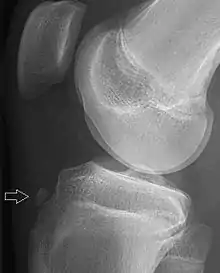

![]() | |

| Avulsion fracture of a fingertip bone | |